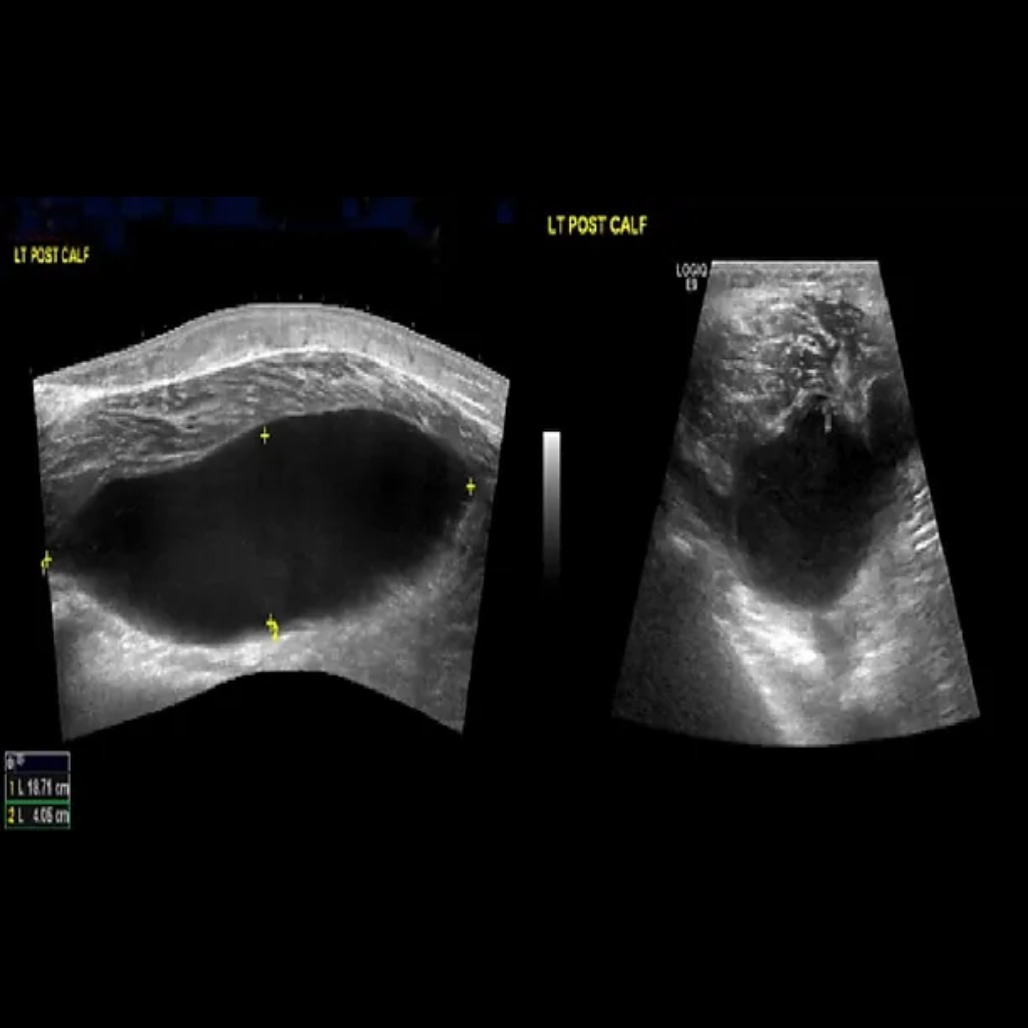

בדיקת דופלר

בדיקה לזיהוי כיוון זרימת הדם, מהירות זרימתו ואיתור חסימות בוורידים ובעורקים.